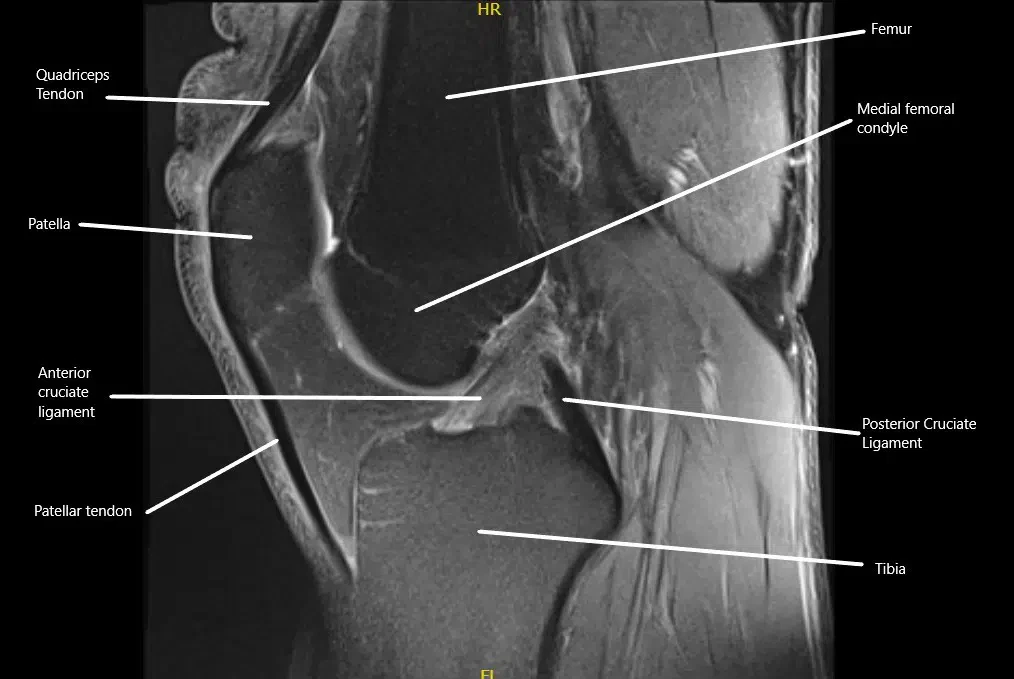

MRI showing the normal cruciate ligaments in the knee joint in the sagittal section.

The posterior cruciate ligament (PCL) is located inside the knee joint, connecting the back of the femur (thigh bone) to the front of the tibia (shinbone). It stabilizes the knee by preventing the tibia from moving too far backward relative to the femur. The PCL works with the anterior cruciate ligament (ACL) and other supporting structures to ensure the knee remains stable during movement, especially when bending or rotating.

To diagnose a PCL injury, the physician will conduct a detailed physical examination and review the mechanism of injury. One common test is the posterior drawer test, where the doctor attempts to move the shinbone backward while the knee is bent, checking for excessive movement. X-rays are used to rule out bone fractures, while an MRI provides a clear image of the soft tissues, including the PCL, to confirm the extent of the injury.

Posterior cruciate ligament is located inside the knee and it attaches the lower end of femur to the upper end of tibia. It courses from the top and in the front to lower down on the back side of the upper end of tibia. It is present behind the anterior cruciate ligament.